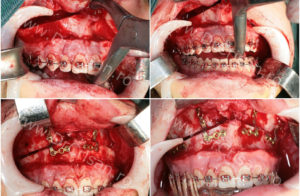

Fotografie realizata în timpul intervenției chirurgicale. Imagini cu fractura controlata a maxilarului, stabilirea raporturilor corecte, imobilizarea maxilarului în noua poziție cu ajutorul unor plăcuțe de osteosinteza.

Fotografii realizate la finalul intervenției chirurgicale (foto stânga “Sutura” – foto dreapta “raport dentar post operator”), urmează restabilirea ortodontica ulterioara a raporturilor ocluzale.